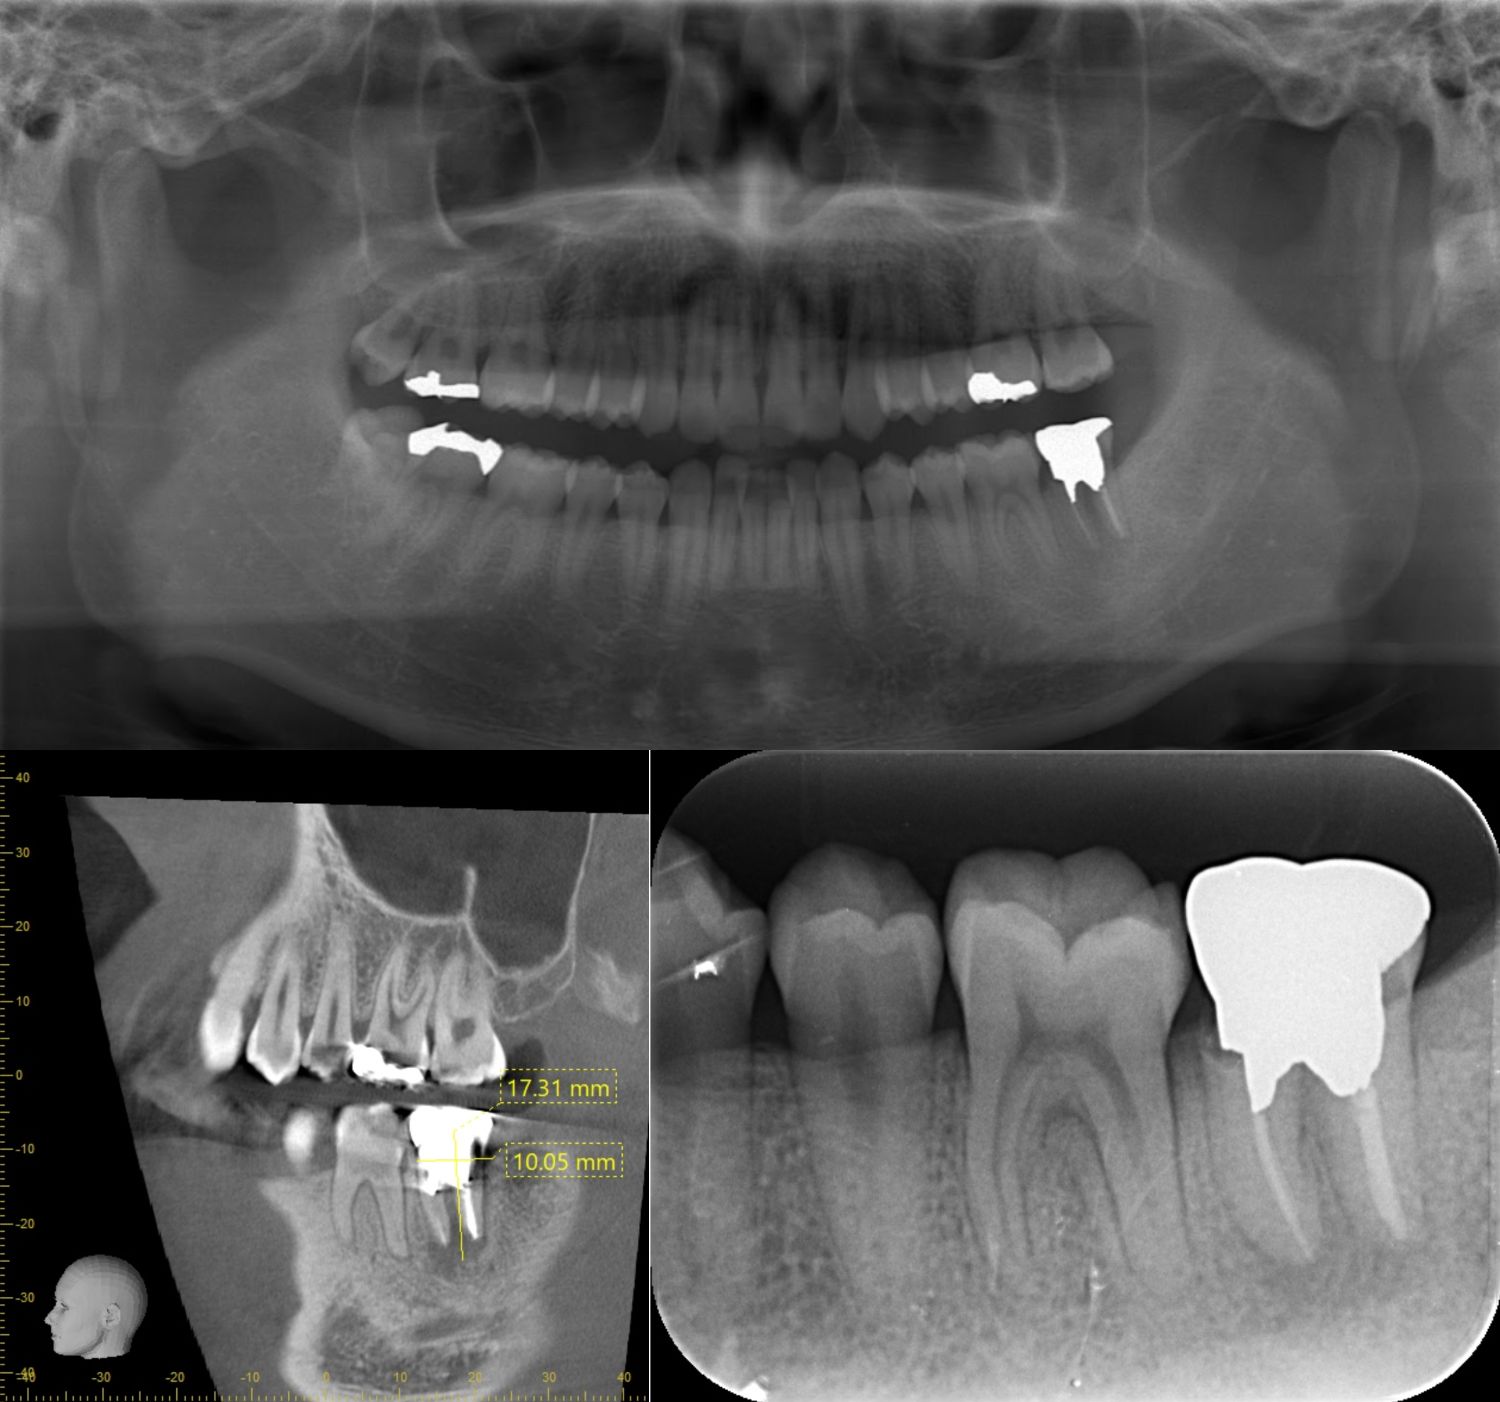

意図的再植(蓄膿症併発したケース) 2019.07.17口腔外科の症例 治療期間:1年費用:意図的再植6万リスク:感染した歯を戻す戻す意図的再植は、骨に再度歯がくっつかなくてはいけないので、正着しない場合がある。処置後鼻血が出る場合がある。 術前の様子右上の歯の根の... 続きを読む